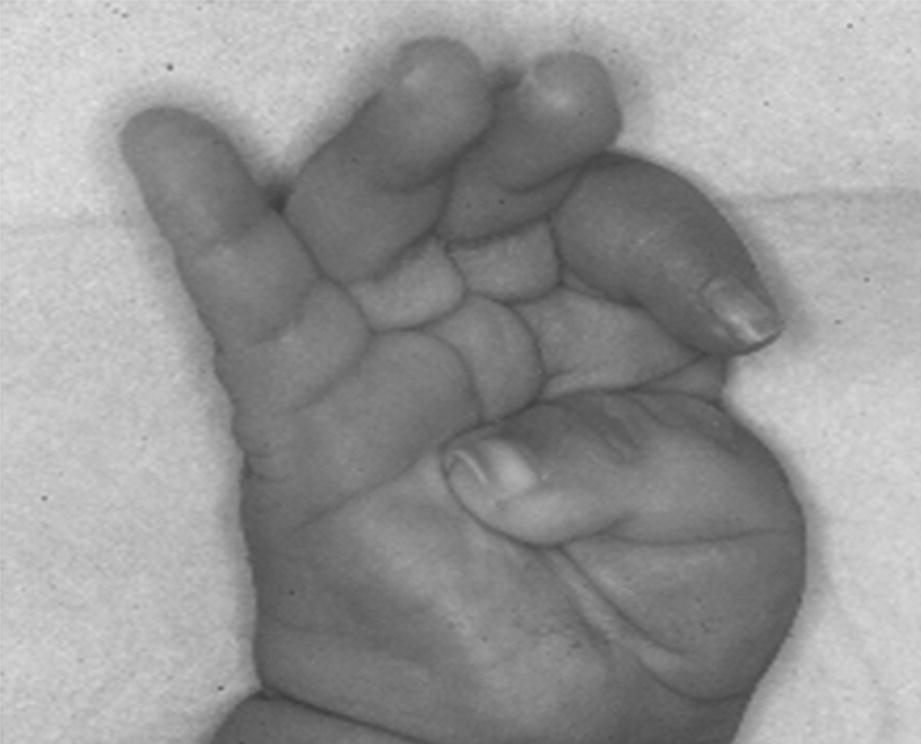

masa syndrome in twin brothers

pdf masa syndrome new clinical

l1 syndrome genereviews ncbi bookshelf

x linked hydrocephalus springerlink

masa syndrome wikipedia